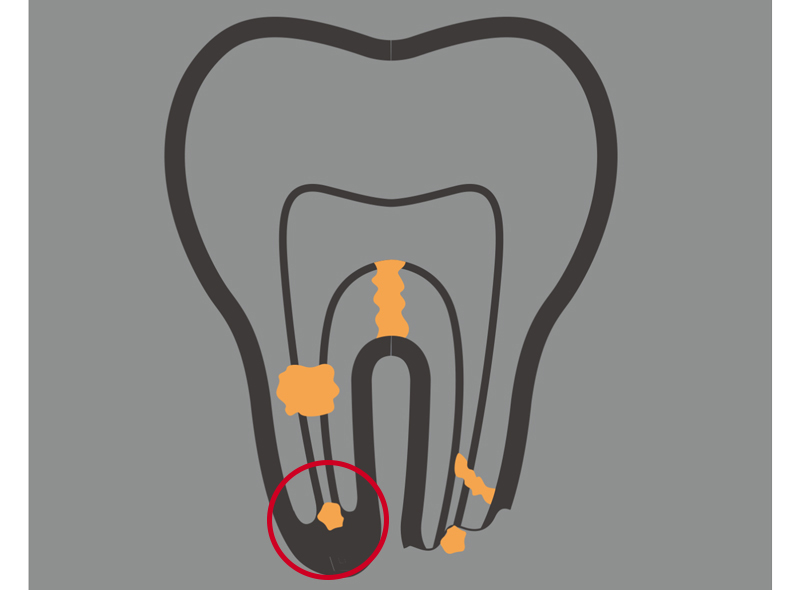

意図的歯牙再植法

意図的再植術とは、保存が難しいと判断された歯を一旦抜去し、お口の外で歯根の病巣除去や根管の清掃といった処置を施した後に、元の歯槽骨に再移植する方法です。

この治療は、歯根膜が健全な場合に抜歯予定だった歯を残せる可能性があります。通常の根管治療では治せない場合や、他の手段が尽きた特殊な症例で適用される最後の選択肢と言えます。

「MTAセメント」の使用で成功率を向上

通常の根管治療や、歯根の先端を外科的に処置する方法でも改善が難しい症例において、抜歯を回避する最後の手段が「意図的歯牙再植法」です。これは、問題のある歯を一度意図的に抜歯し、口腔外で歯根の病変部を切除・殺菌洗浄したのち、元の場所へ戻し保存する高度な治療法です。

当院ではこの逆根管充填にMTAセメントを用いることで、治療の成功率を大幅に向上させています。

MTAセメントが持つ極めて高い封鎖性は、根管内からの細菌の漏洩を確実に遮断します。優れた生体親和性と硬組織誘導能で、歯を支える顎の骨の再生を積極的に促進します。